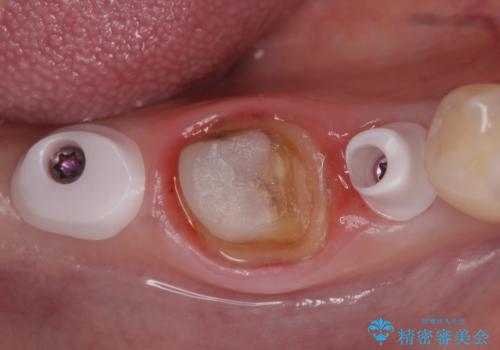

右下7は欠損しており、右下5は保存不可能だったため、インプラントによる欠損補綴を行いました。

インプラント埋入時には骨が不十分な部位に骨増生を行っております。